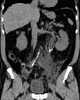

Calculus in calyceal diverticulum